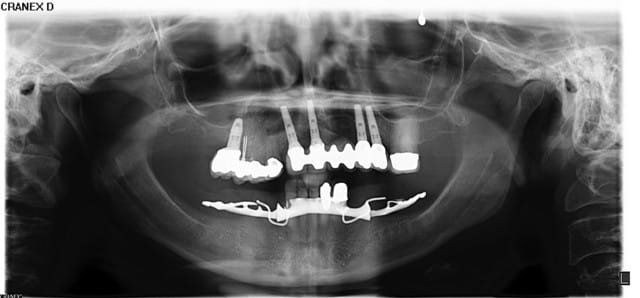

Patiente adressée pour évaluation :

son dentiste ne sait que faire.

À l'examen :

13 : belle fistule vestibulaire, mobilité, carie cervicale

14 : mobilité +++

15 : fracture racine (?), carie cervicale

Les implants datent de 5-6 ans (par un autre CD, la patiente a depuis déménagée).

Le bas , pas touche cette année, on verra en 2012.

Votre plan de tx ?

Panorex avec Vitallium en bouche ok... au moins on sait que la patiente possède un partiel...